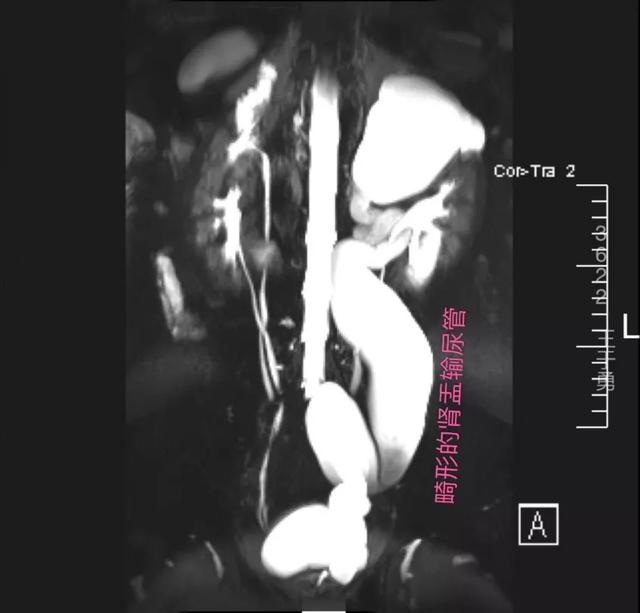

经过王于勇细致的病史采集、体格检查和针对性的检查,确诊小徐患的是双侧重复肾重复输尿管畸形。

据王于勇介绍,这是一种较罕见的先天性泌尿系畸形疾病,单侧较双侧者多,且由于下段输尿管末端盲端位于前列腺部尿道,导致左侧上半肾重度积水无功能,更是增加了治愈难度。

小徐的肾脏影像图

「一般来讲,双侧重复肾重复输尿管畸形患者,只要功能正常,没有明显临床症状,可不做特殊处理。但通过超声和 CT 来看,这位患者已经出现了重度积水,严重影响到肾脏功能,我们就必须对其进行『修补』与『重建』,阻止肾功能的进一步损害。」王于勇对我们进一步解释。